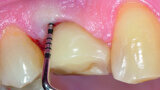

Fig. 1a: Implant in position #14 affected by peri-implantitis: periimplant probing a) with the prosthetic crown in situ and b) after prosthetic crown removal.